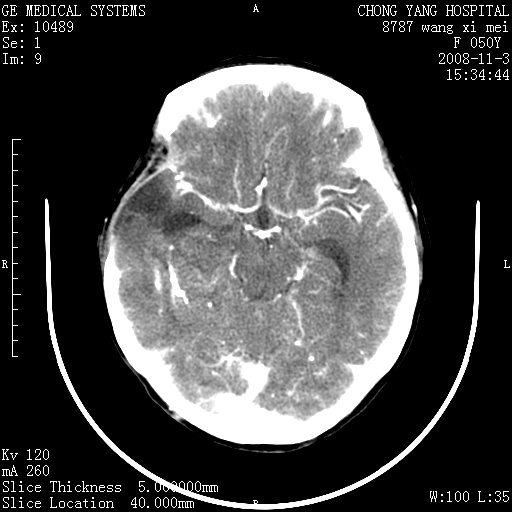

右侧颞顶部可见低密度实变影,内见不规则钙化灶,边界不清,占位效应明显,侧脑室后角受压移位,符合胶质瘤术后复发改变。

右颞骨局限性缺如,局部脑组织无外隆。右颞叶可见片状脑脊液样低密度影,边缘较清,右侧侧脑室三角区可见一块状等密度影,且伴有强化,余未见明显异常改变。

考虑:右大脑术后改变伴肿瘤复发。

手术后局部片状低密度改变(软化灶),其后方颞叶似等密度病灶,界限不清,内见钙化,有轻度占位效应,但增强后强化之血管走行如常。应不考虑:复发!

考虑右侧颞顶叶胶质瘤术后复发。

应考虑肿瘤复发,右颞顶叶已出现轻度强化肿块.必要时可与原片比较以下.

右侧颞顶部混杂密度影,内有钙化,有占位效应。应该是复发灶。结合术后片更好。